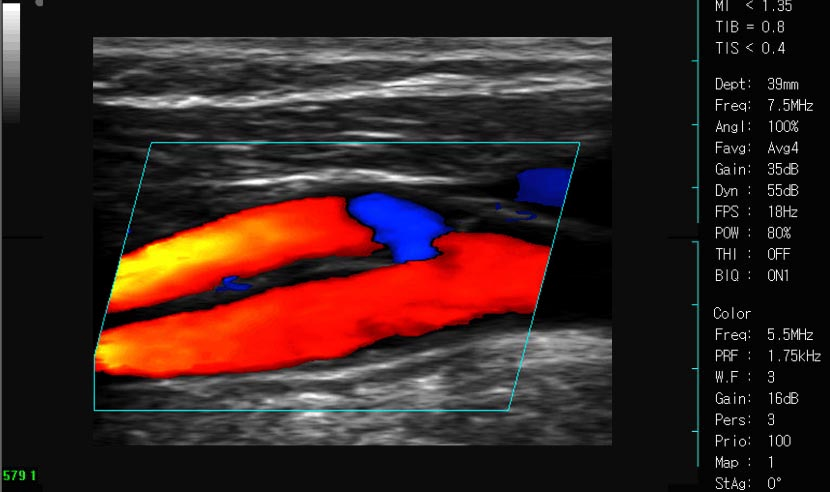

Цветная допплеровская ультразвуковая диагностическая система для животных FDC8100V применяет ведущие в мире основные технологии, интегрирован современный эргономичный дизайн. Превосходное качество изображения и чувствительность на кровоток, обширные возможности адаптации зондов, могут удовлетворить потребности в диагностике лошадей, коров, баранов, свиней, собак и кошек и других животных.

Эмиссия плоских волн, параллельный прием и обработка 16 пучков волн, значительно улучшает частоту кадров изображения B+C, B+C+D и чувствительность на кровоток, и дает настоящий прикладной дисплей «три синхронизации».